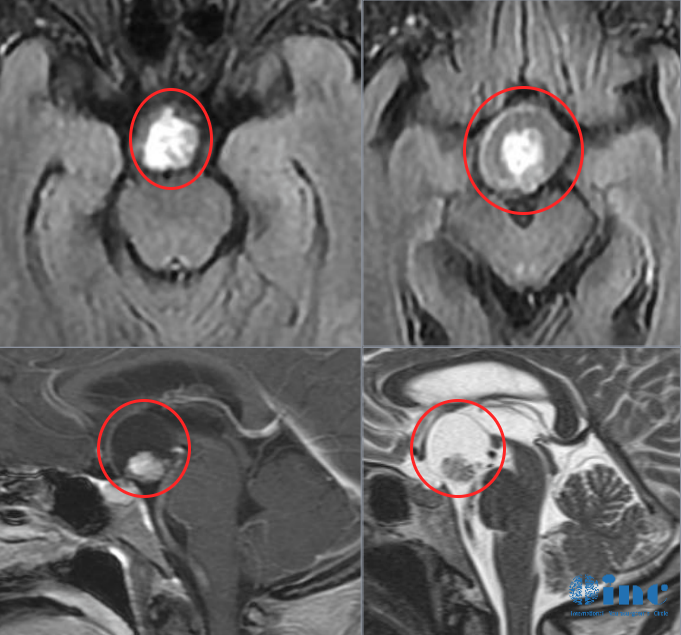

据李奶奶回忆,2023年1月因肺部感染住院,发现短暂视物模糊以及记忆力减退等症状,对于健康一直都比较重视的她进行颅脑磁共振检查。鞍上区占位性病变,颅咽管瘤可能性大。眼科检查后,确实双侧视野同侧缺损(左侧),视物模糊,可能是脑子里的这颗肿瘤造成的。

▲术前术后影像对比,红色为术前肿瘤位置,绿色为术后切除效果